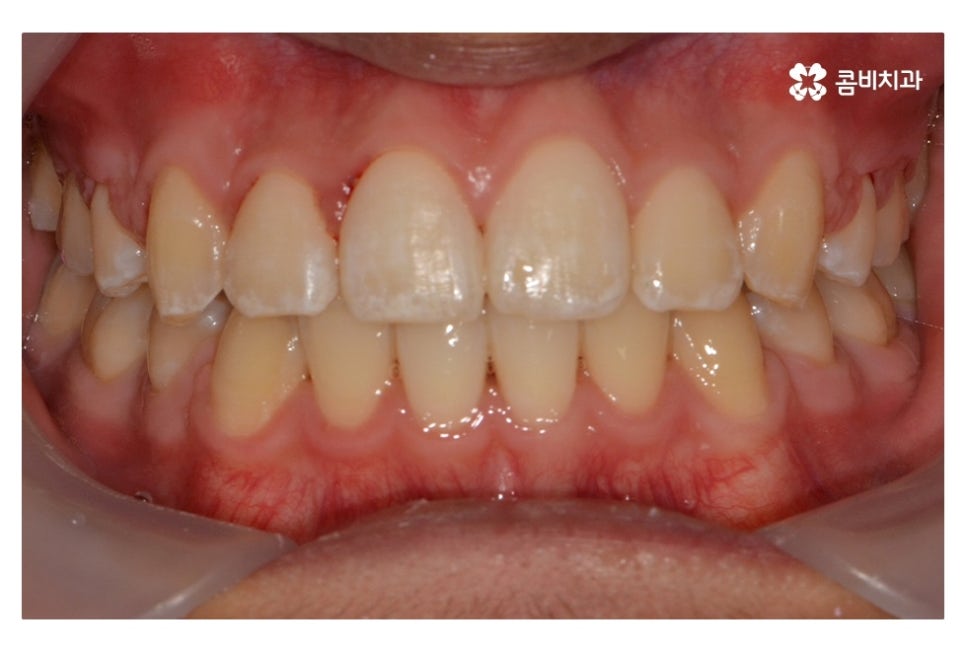

오늘 보여드릴 중학생치아교정 사례의 경우에는

악골의 위치는 정상적인 상태에서 불규칙한 치열로 인해

교정 치료를 진행한 사례라고 할 수 있어요.

위 환자분의 경우 발치가 진행된 사례로 치아의 이동 공간을

고려할 때 발치가 필요했고 환자분도 보다 나은

심미성을 위해서 동의한 상황이라고 할 수 있어요.

위 사진에서 보시면 시간이 지나면서 발치를 했던 치아의

공간이 사라지고 교정을 통해서 치열이 가지런해진 것을 확인할 수 있는데요.

중학생치아교정에 있어서 중요한 사항이 단지 치열만이

가지런해 보이는 것이 아닌 얼굴과의 조화와 교합이라 할 수 있어요.